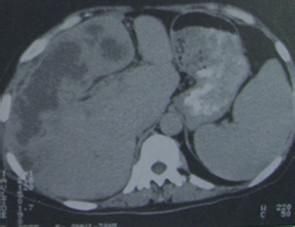

2. CT掃描的圖像比較清晰,不受肥胖、腸道氣體和操作者的主觀因素影響。

CT能客觀地顯示腫瘤的部位和大小,腫瘤與周圍組織的關係;顯示肝葉的形態改變(肥大或萎縮),腫瘤與尾葉的關係;擴張的左、右肝管間連續性中斷,能提供準確的梗阻水平及肝內膽管擴張徵象。增強掃描可使組織結構 為清晰。螺鏇CT可以獲得人體解剖結構無間斷的圖像信息,將這種特殊的圖像採集方法和靜脈注射造影劑相結合,用多種圖像處理方法顯示血管影像。因此螺鏇CT可以代替血管造影顯示門靜脈系統結構,了解門靜脈系統的受累情況。